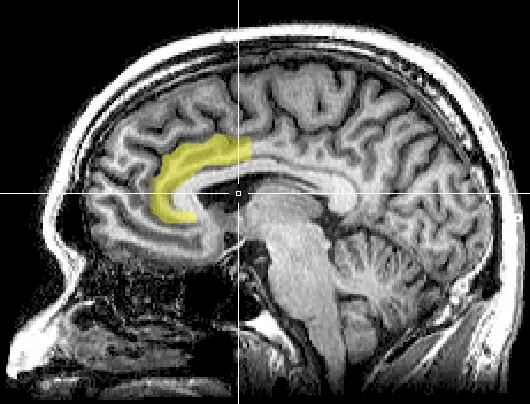

با "کورتکس میانه قدامی" مرکز کنترل اراده آشنا شو

همه‌چیز از آموزش "کورتکس میانه قدامی" مغزت شروع میشه.

می‌تونی مثل یه عضله اون رو تقویت کنی. کورتکس میانه قدامی وقتی رشد می‌کنه که به طور مداوم کارهای سختی رو که نمی‌خوای انجام بدی، انجام بدی.

یعنی اراده یه مهارته که می‌تونی یاد بگیری، نه ویژگی‌ای که باهاش به دنیا میای. می‌تونی این بخش رو آموزش بدی که بزرگتر و قوی‌تر بشه.